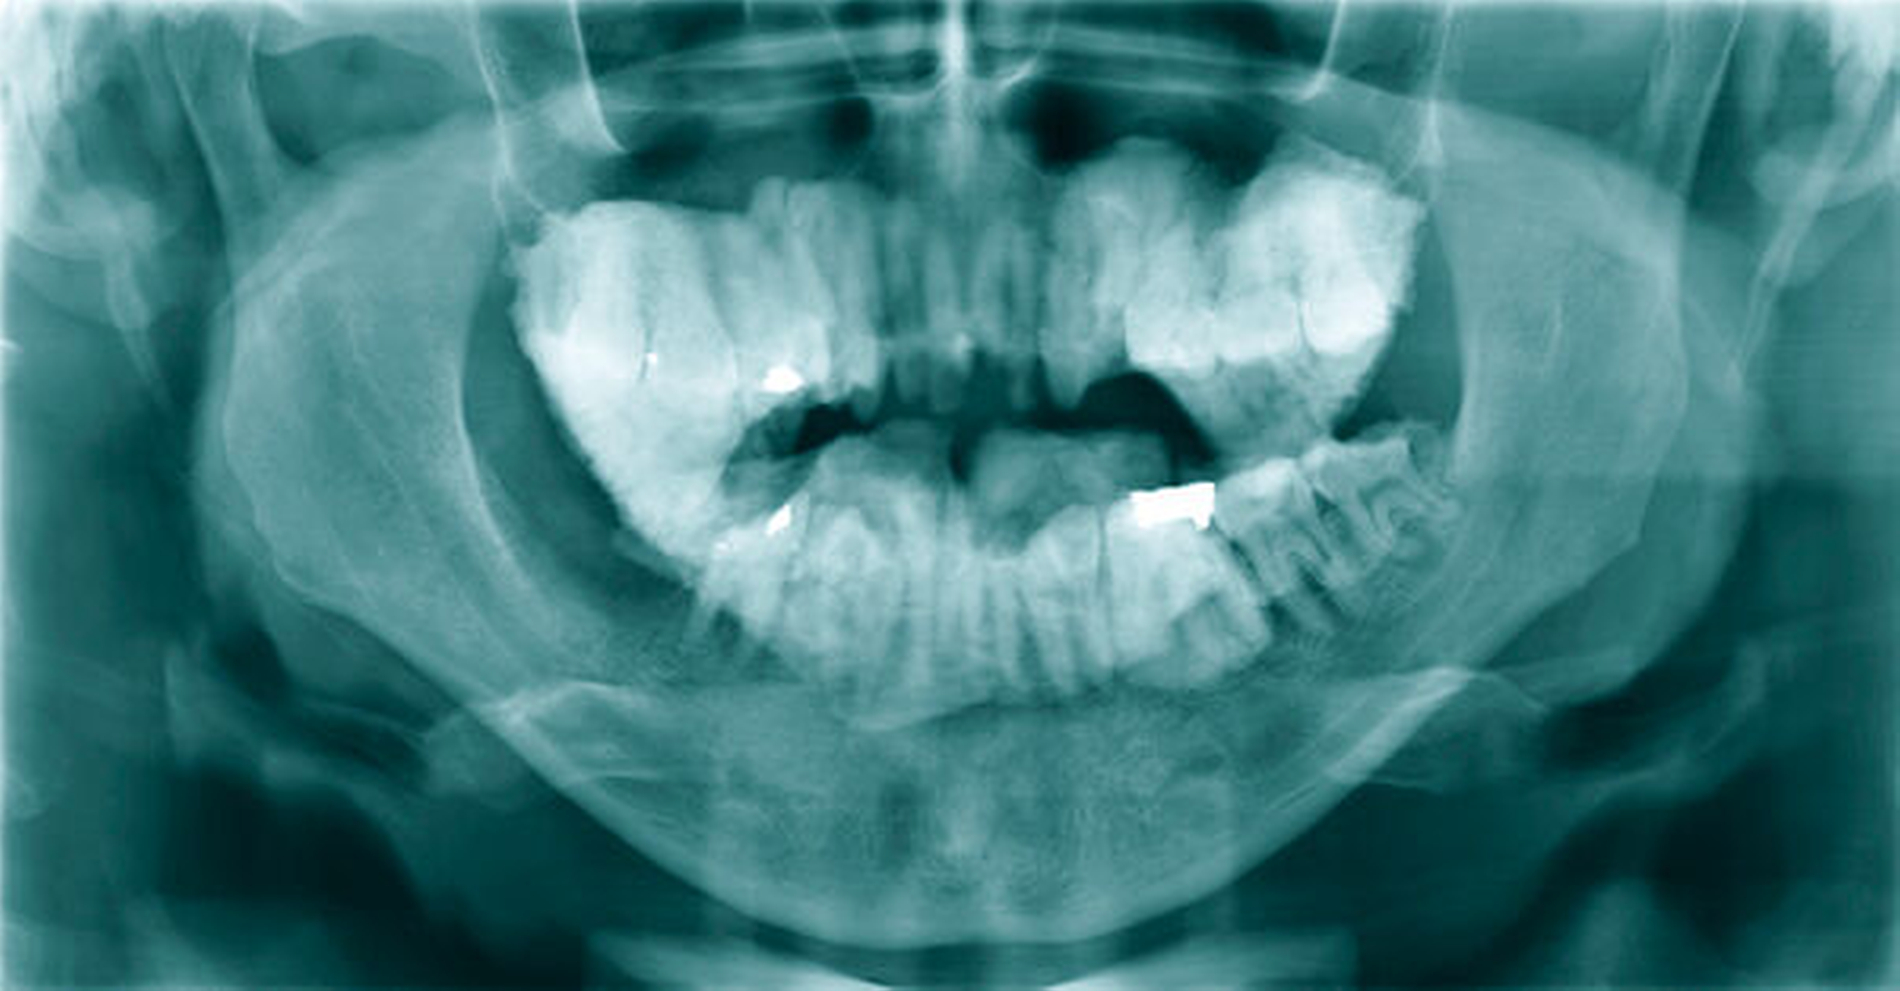

In der Folge leiteten wir eine intravenöse Antibiotikatherapie ein und nahmen den Patienten stationär auf. In der durchgeführten Röntgendiagnostik (OPG) zeigte sich eine Aufhellung im gesamten zahntragenden Bereich beider Kiefer (Abbildung 6). Die Beurteilung der Zahnwurzeln stellte sich mitunter als sehr schwierig dar.